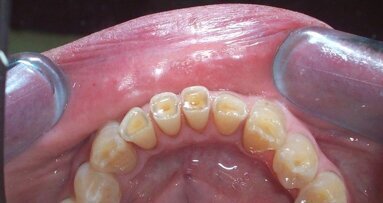

Sì: nella sensibilità del clinico odontoiatra è emergente il fatto che smalto e dentina non possono ridursi solo per una eziopatogenesi cariosa. L’usura, infatti, è sempre più oggetto di attenzione nella ricerca e ai convegni, ma soprattutto nella clinica dove l’odontoiatra osserva sempre e guida il paziente verso un corretto percorso di prevenzione e cura delle usure.

È stata riscontrata un’insufficiente capacità di contrastare la discesa del pH in soggetti affetti da erosione. La capacità tampone della saliva sembra quindi avere un ruolo fondamentale nei casi di erosione.